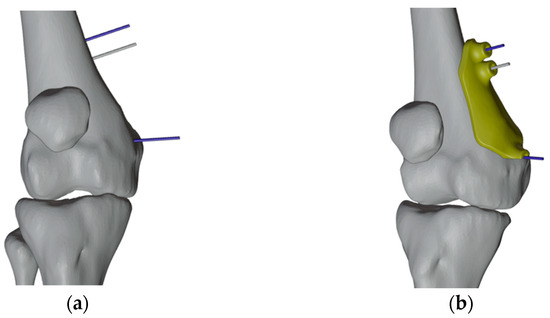

2.4. Design and Production of the Patient-Specific Instrumentation

2.4.1. PSIs Design for the Right Femur

2.4.2. PSI Design for the Left Femur